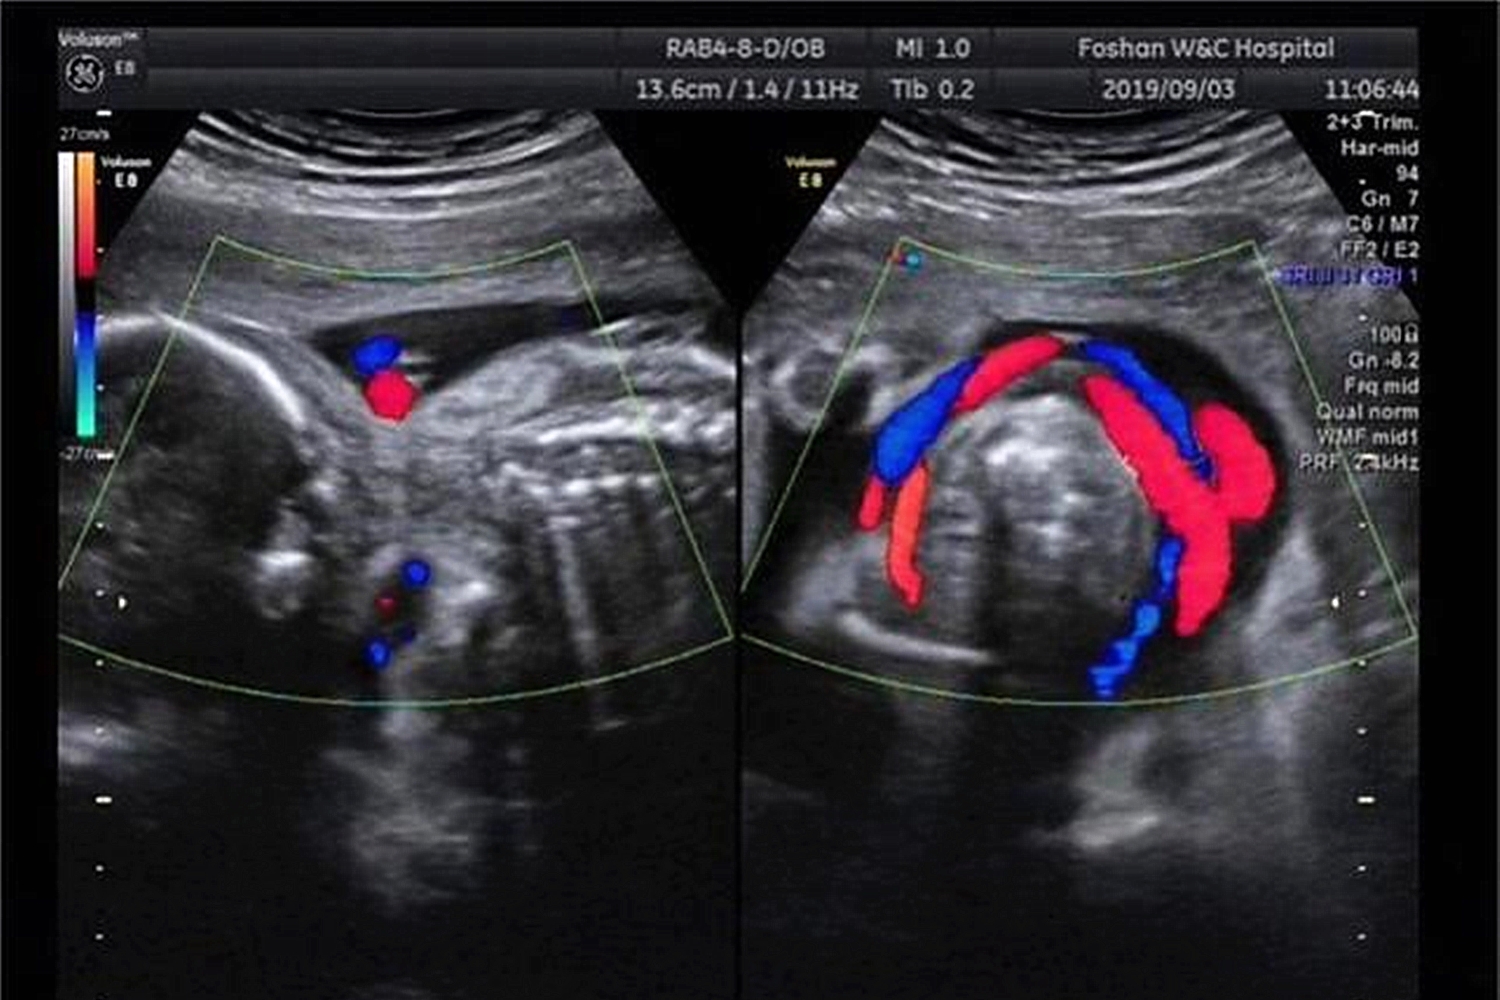

但在刘静妊娠第24周产检时,医生通过四维彩超检查,发现胎儿现况,当时胎儿的情况是脐带绕颈一周,且通过四维彩超和黑白彩超发现在胎儿的旁边有“脐带有打结”的现象。

“脐带有打结”针对胎儿来说是非常危险的事情。一旦胎儿动得厉害,脐带的结被打死了,只需短短几分钟,胎儿就会面临窒息的危境。

脐带是胎儿的营养的供给通道,脐带打结后营养将无法再输送到胎儿体内,最终胎儿将会终止发育胎死腹中。

脐带打结分为真结和假结,其实在生活中真结并不多见。

真结产生的原因是由于宫内的脐带生长过长,在内部形成一个环套而胎儿在生活在那个发育时,穿过了环套,打成了一个结扣。

但一般在未拉扯的情况下,脐带还是宽松的环绕在宫腔内,对胎儿是没有影响的,若结扣有逐渐打死的趋势使血液循环受阻,影响胎儿发育严重时会发生胎儿死亡的危险。

假结就是脐带在宫腔内显现堆叠现象,在彩超中无法确认内部是否有结,一般假结是没有危险的,很少会有血管破裂出现。